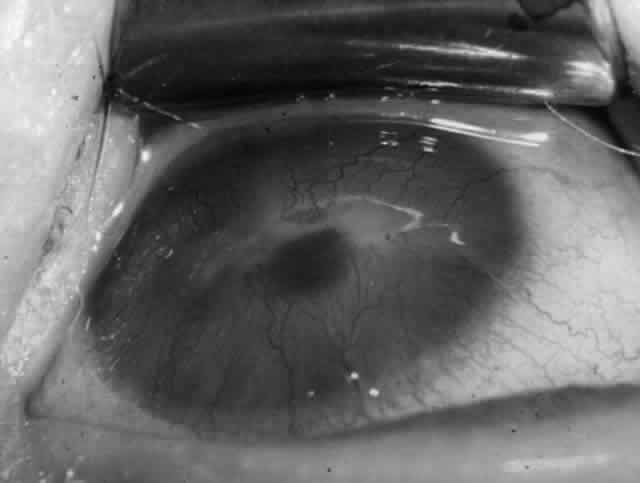

Clinically, the ocular disease in cicatricial pemphigoid (OCP) may present unilaterally in the form of a chronic, recurrent catarrhal conjunctivitis, but it eventually becomes bilateral. Subepithelial fibrosis is characteristic of stage 1 of OCP (Fig. 7). Stage 2 shows fornix foreshortening (Fig. 8), and symblepharon formation is the hallmark of stage 3 (Fig. 9). Stage 4, end-stage disease, is characterized by ankyloblepharon and surface keratinization (Fig. 10). Obstruction of the lacrimal ductules and meibomian gland ducts eventually produces an unstable tear film and progressive sicca syndrome, but it is to be emphasized that OCP is not a dry-eye syndrome until late in the disease course.20 Trichiasis and entropion occur because of the subepithelial fibrosis, with eventual keratopathy, corneal neovascularization, and corneal ulceration and scarring.20

Fig. 9. Stage 3 of an eye affected by cicatricial pemphigoid. The conjunctival “shrinkage” continued and a frank symblepharon developed.